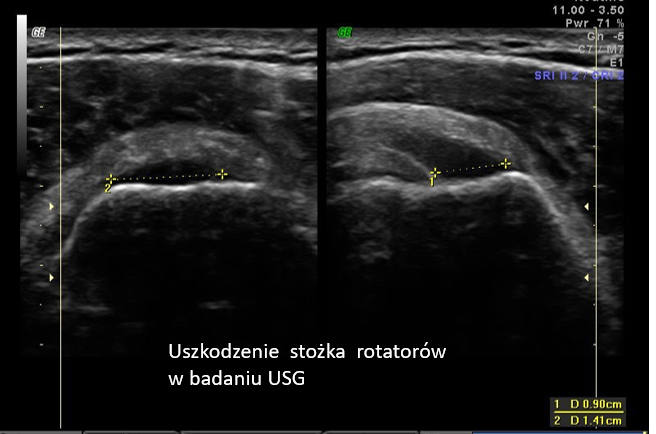

1. Uszkodzenia stożka rotatorów

To najczęstsza przyczyna bólu barku. Stożek rotatorów obejmuje cztery mięśnie i ich ścięgna, które stabilizują staw.

USG pozwala wykryć:

- częściowe i całkowite zerwania ścięgien

- tendinopatie (zmiany przeciążeniowe)

- degenerację włókien ścięgnistych

W praktyce: nawet niewielkie uszkodzenia mogą być widoczne w badaniu USG, szczególnie przy zastosowaniu techniki dynamicznej.